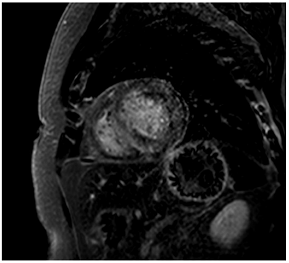

To avoid the low but important risks of endomyocardial biopsy, which can have an overall complication rate of up to 6% [2], myocardial fibrosis can be assessed non-invasively using CMR: LGE is suitable for detecting irreversible replacement fibrosis and myocardial scarring and T1/ECV mapping for detection of potentially reversible (reactive) interstitial and more diffuse fibrosis (not detectable by LGE) (Figure 2).

9. Tissue Characterisation with Late Gadolinium Enhancement

LGE has become the reference standard for non-invasive imaging of myocardial scar and focal fibrosis [40]. Gadolinium chelates are interstitial agents that cannot penetrate healthy intact cell membranes. Therefore, they remain in the interstitial space and accumulate in areas of cell injury/necrosis and focal fibrosis where this is expanded, while in healthy regions, contrast more readily washes out [41]. Specific LGE patterns are seen in different diseases (e.g., subendocardial fibrosis in CAD, patchy epicardial/mid-wall fibrosis in areas of hypertrophy in HCM). Minor areas of LGE can be detected in up to 50% of patients with HHD, but there is no specific pattern (in 95% of the non-ischaemic LGE distribution) [42]. If present, LGE is often found in the basal to mid-septal, inferior, and inferolateral segments in patients with HHD [42]. The severity of diastolic dysfunction increases with the extent of fibrosis by LGE [25,31]. Furthermore, focal fibrosis/LGE may be a substrate for ventricular arrhythmia and is associated with sudden cardiac death [31].

10. Tissue Characterisation with T1 and Extracellular Volume (ECV) Mapping

LGE allows the detection of focal alterations in the myocardium, but diffuse fibrosis may go undetected on LGE imaging. Tissue characterisation with parametric mapping methods such as T1 and ECV mapping has the potential to detect and quantify both focal and diffuse alterations in the myocardial structure. Furthermore, changes in the myocardium over time may be assessed longitudinally [40]. Estimation of myocardial ECV (interstitium and extracellular matrix) requires the measurement of myocardial and blood T1 before and after the administration of contrast agents, as well as the patient’s haematocrit. ECV can then be calculated using the formula:

Myocytes account for approximately one-third of all cells in normal myocardium. The remaining two-thirds of cells include endothelial and vascular smooth muscle cells and fibroblasts in interstitial/perivascular spaces [2] (Figure 2). Normal CMR ECV values vary between 25.3 and 3.5% [43]. Ideally, age- and sex-corrected normal values for ECV should be used [44]. Hypertension affects both the cellular and extracellular compartments of the myocardium. In addition to cardiomyocyte hypertrophy, in HHD, fibrous tissue (primarily type I fibrillar collagen) is deposited in the extracellular matrix over time and leads to increased tissue stiffness (i.e., diastolic dysfunction) [2]. ECV values are higher in hypertensive patients with LVH than in patients without LVH, and eccentric forms of hypertrophy seem to have the most fibrosis and highest ECV values, together with more pronounced systolic impairment and are associated with a poor cardiovascular prognosis (Figure 1) [2,6]. CMR-derived T1 mapping and strain analysis seem to be related, but an adequate comparison of the performance of these parameters is often limited due to the lack of harmonization of measurement methods [35]. Furthermore, ECV values seem to correlate with many blood biomarkers associated with (i) systemic inflammation; (ii) metabolism; (iii) fibrosis; (iv) chemotaxis; and (v) platelet activation [6]. This may suggest that an increase in ECV in hypertensive patients is a (non-specific) imaging biomarker of inflammation, tissue remodelling, atherogenesis, or metabolic disorder in patients with HHD [6]. Given the clinical consequences of myocardial fibrosis in HHD and considering the potential for recovery of fibrosis with appropriate treatment, the need for an accurate diagnosis of myocardial fibrosis is apparent.

Although tissue characterisation with native T1 and ECV has been shown to have incremental diagnostic benefits even in very early disease stages (e.g., diffuse fibrosis not detectable by LGE), there is an overlap between different cardiomyopathies and some overlap with normal T1 values. The difference in ECV between normal subjects and patients with HHD is small (0.29 ± 0.03 vs. 0.27 ± 0.02) [2]. Furthermore, other pathologies in addition to fibrosis increase ECV values such as myocardial inflammation or amyloid deposition. As with all medical parameters, abnormalities in native T1 and ECV need to be interpreted within their clinical context and pre-test probabilities and in conjunction with established CMR techniques such as LGE. Nevertheless, native T1 and myocardial ECV mapping seem to be promising imaging biomarkers to characterise HHD and eventually may even help to guide and monitor treatment response with antifibrotic agents in certain hypertensive individuals. Non-ischaemic LGE is associated with adverse LV remodelling, worse function, and elevated markers of wall stress and myocardial injury. Reactive interstitial fibrosis is potentially reversible with targeted therapies [45]. It is increasingly appreciated that the identification of focal or diffuse fibrosis may have significant independent prognostic implications and may help in monitoring disease progression and guiding anti-fibrotic therapies in the future [46].